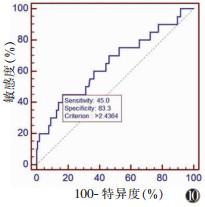

以敏感度为纵坐标,1-特异度为横坐标,分别绘制双侧SCM厚度差绝对值与SCM比率的ROC曲线,分别以双侧厚度差值≥0.74 cm和双侧厚度比率≥0.24为临界值,预测DDH的敏感度分别为50.0%和45.0%,特异度分别为77.6%和83.3%(图 9,10)。

| 图 10 SCM比率ROC曲线下面积为0.648,以双侧SCM比率≥0.24为临界值,测得敏感度和特异度分别为45.0%与83.3% |